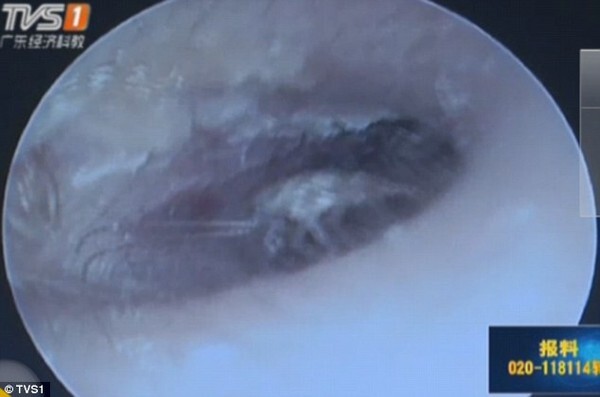

Hình ảnh con gián trong tai bệnh nhân qua máy nội soi. |

Cuối cùng cô đã đến khám tại phòng khám nội soi tai mũi họng của bác sĩ chuyên khoa Meng Jie, người cho cô biết có một con gián còn sống nguyên ở trong tai của cô.

Các bác sĩ đã dùng thuốc gây tê tại chỗ để phun vào con gián nhằm khiến nó bất động trong chốc lát để tiện kéo nó ra.

Khi các bác sĩ kẹp con gián và cẩn thận kéo nó di chuyển ra khỏi tai bệnh nhân, cô Su đã hét lên.

Kết quả là con gián to tướng đã được kéo nguyên lành (không thiếu cái chân nào, thật may mắn) và sống nhăn ra khỏi tai bệnh nhân.